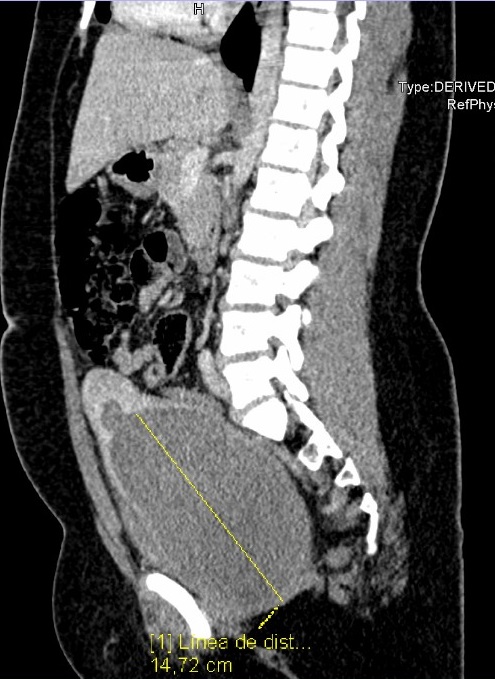

Se solicita posteriormente una resonancia magnética nuclear pélvica en al que se evidencia un útero doble (didelfo) y dos hemivaginas con la izquierda obstruida (Fig. 2).

Figura 2. Resonancia magnética